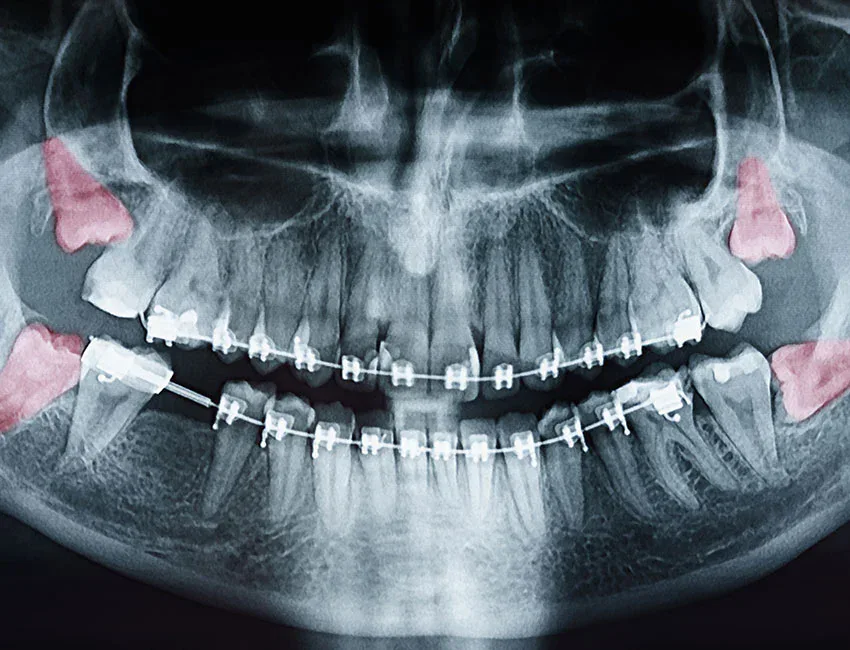

- Impacted wisdom teeth—those trapped beneath the gum or jawbone—can lead to pain, infection, cysts, and damage to neighboring teeth.

- Impaction: When wisdom teeth can’t fully emerge, they become trapped beneath the gum or jawbone. Impacted teeth can grow at angles, pushing against adjacent teeth and causing pain, swelling, and potential damage to tooth roots.

- Cyst formation: In rare cases, impacted wisdom teeth can lead to cysts that damage the jawbone, nerves, and surrounding teeth if left untreated.

Regular dental X-rays can reveal problems invisible to the eye, such as impaction, cysts, or decay developing beneath the surface. Your dentist can monitor changes over time and recommend intervention before complications escalate.